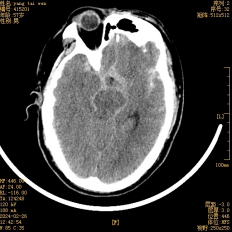

入院時(shí)頭顱CT提示:蛛網(wǎng)膜下腔出血(出血集中在環(huán)池、側裂池及縱裂池,如箭頭所示)